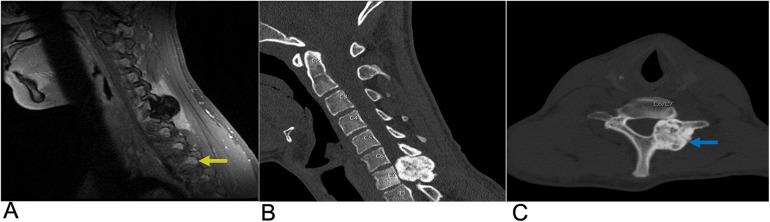

Spinal lesions encompass a diverse range of pathologies, including primary and secondary tumors, infectious processes, vascular malformations, traumatic injuries, and degenerative conditions, each with distinct imaging characteristics crucial for accurate diagnosis and management. Imaging plays vital roles in assessing lesion morphology, anatomical localization, and neurological impact, guiding clinical decision-making and therapeutic planning. This review systematically explores spinal lesions based on their anatomical compartments, highlighting key radiological features and providing a comprehensive reference for radiologists.

脊柱病变包括多种病理情况,包括原发性和继发性肿瘤、感染性病变、血管畸形、创伤性损伤以及退行性疾病,每种病变都具有独特的影像学特征,这些特征对于准确诊断和治疗至关重要。影像学在评估病变形态、解剖定位和神经影响方面发挥着至关重要的作用,指导临床决策和治疗规划。本综述基于解剖分区系统地探讨脊柱病变,突出关键的放射学特征,并为放射科医生提供全面的参考。